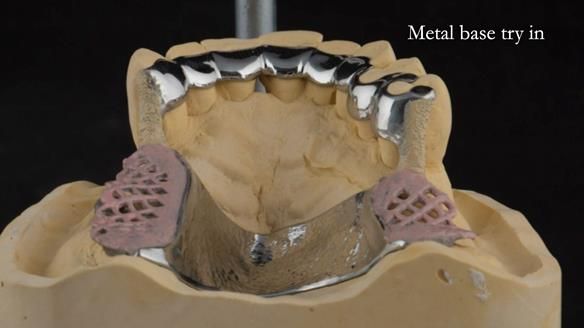

A metal-based upper RPD was made,

with metal backings incorporated to future-proof the design

should further teeth fail.